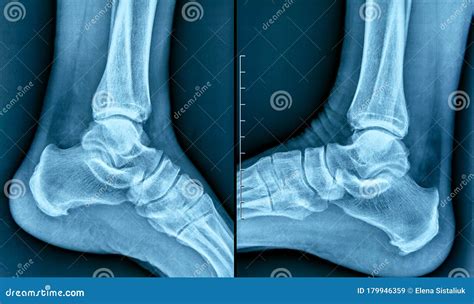

A heel spur, technically known as a calcaneal spur, is a bony protrusion that develops on the underside of the heel bone. Over time, calcium deposits build up on the heel, resulting in this outgrowth. These spurs are often associated with plantar fasciitis, a common condition that involves inflammation of the tissue running along the bottom of the foot.

It is important to note that many individuals possess heel spurs without ever experiencing any pain. The pain often stems not from the spur itself, but from the associated inflammation of the soft tissues surrounding the heel bone. This is precisely why a Heel Spur X Ray is ordered—to visualize the bone structure and help the physician determine whether the spur is the primary culprit or if other factors are contributing to your symptoms.

• Visualization: It provides a clear, high-contrast view of the heel bone, allowing the doctor to see the exact size and location of any bony growth.

• Rule Out Other Conditions: An X-ray helps doctors rule out other potential causes of heel pain, such as stress fractures, arthritis, or other bone abnormalities.

Once the radiologist examines your Heel Spur X Ray, they will generate a report for your doctor. It is common for the report to confirm the presence of a "calcaneal spur." However, as mentioned previously, this does not automatically mean the spur is causing your pain. Your physician will correlate these findings with your physical symptoms. For instance, if your pain is worst in the morning or after long periods of sitting, the clinical focus will likely remain on treating the underlying plantar fasciitis, even if a spur is visible.